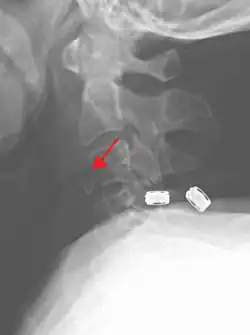

On CT scan or X-ray, a cervical fracture may be directly visualized. In addition, indirect signs of injury by the vertebral column are incongruities of the vertebral lines,[7] and/or increased thickness of the prevertebral space:[8]

-

![CT scan with upper limits of the thickness of the prevertebral space at different levels[8]](./_assets_/CT_of_prevertebral_space.jpg)